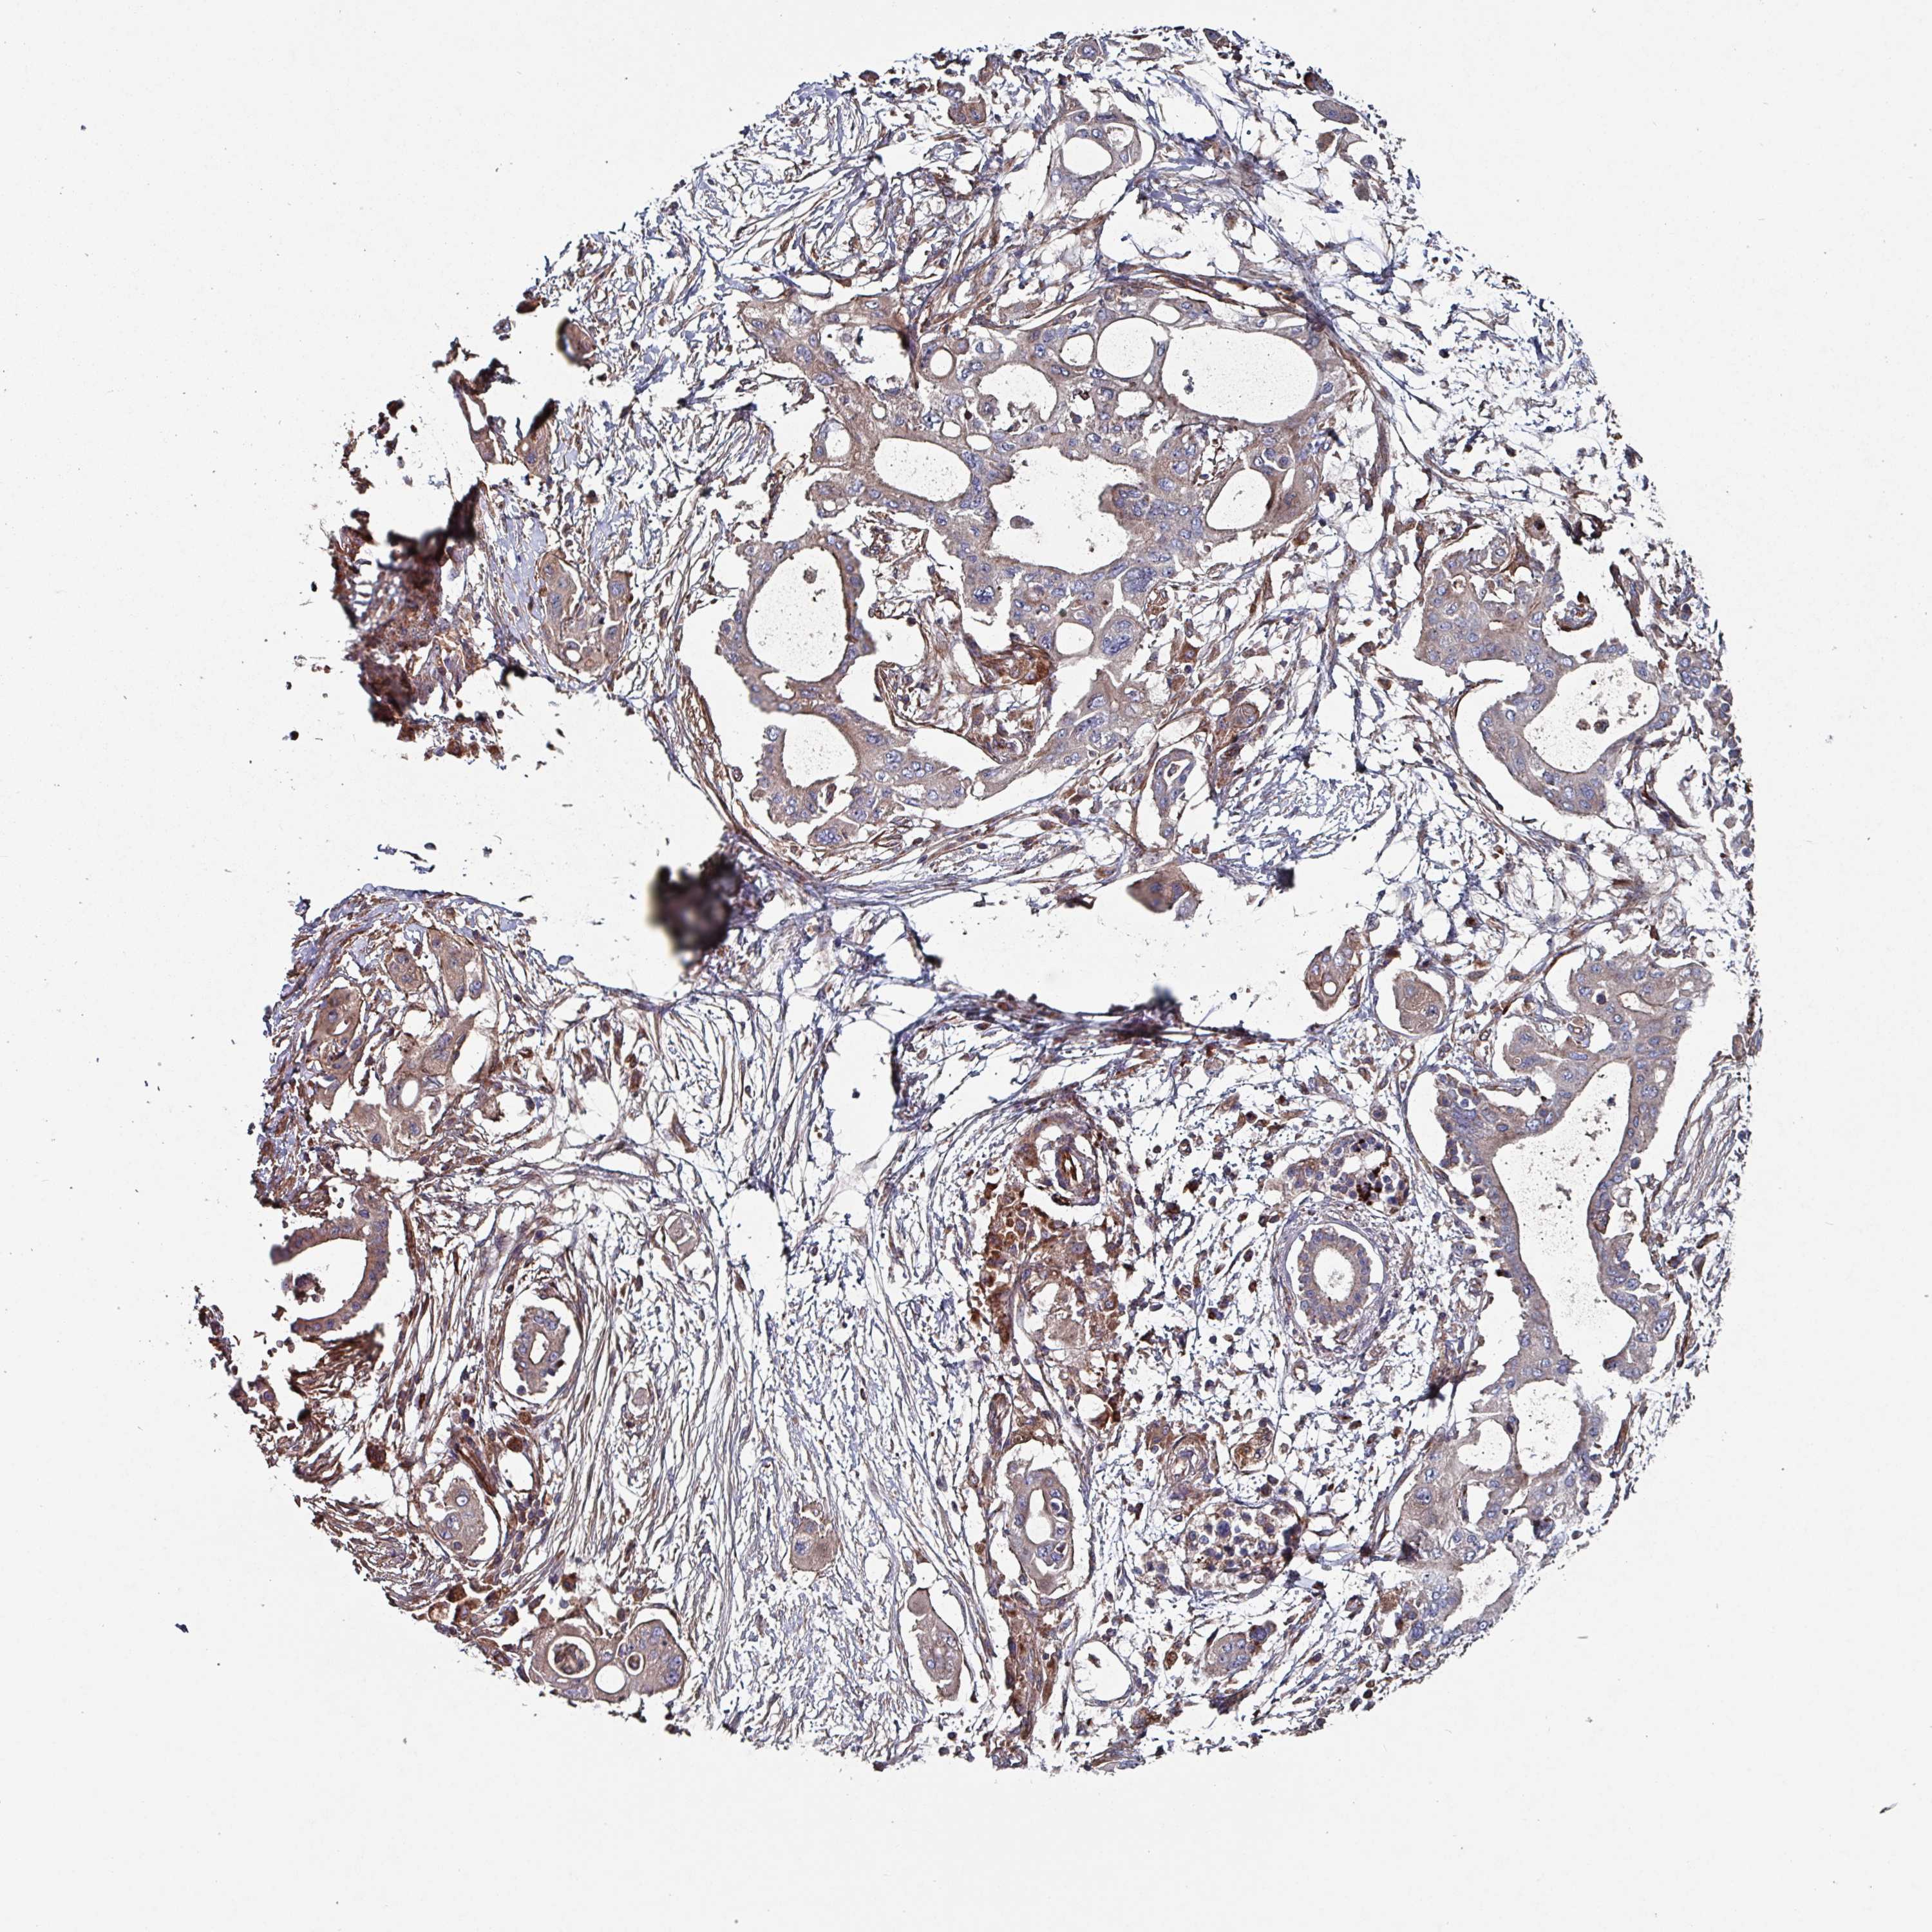

PANCREATIC CANCER - Protein expressioni

A mouse-over function shows sample information and annotation data. Click on an image to view it in a full screen mode. Samples can be filtered based on level of antibody staining by selecting one or several of the following categories: high, medium, low and not detected. The assay and annotation is described here.

Note that samples used for immunohistochemistry by the Human Protein Atlas do not correspond to samples in the TCGA dataset.

Antibody stainingi

Antibody staining in the annotated cell types in the current human tissue is reported as not detected, low, medium, or high, based on conventional immunohistochemistry profiling in selected tissues. This score is based on the combination of the staining intensity and fraction of stained cells.

Each image is clickable and will lead to virtual microscopy that enables deeper exploration of all samples and also displays staining intensity scores, fraction scores and subcellular localization as well as patient and tissue information for each sample.

Antibody HPA051569

Staining

High

Medium

Low

Not detected

Intensity

Strong

Moderate

Weak

Negative

Quantity

>75%

75%-25%

<25%

None

Location

Nuclear

Cytoplasmic/membranous

Cytoplasmic/membranous,nuclear

Adenocarcinoma, NOS